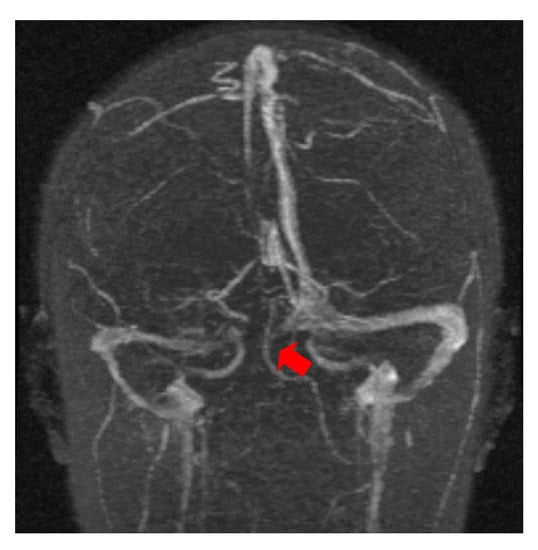

The second case was a female, 31 years old, with an etiology of thrombophlebitis accentuated by the presence of the MTHFR C677T gene polymorphism- homozygous phenotype. The patient was hospitalized with superficial coma, generalized seizures and left hemiparesis. In the course of evolution, subsequent to the cerebral post thrombotic syndrome and edematous encephalopathy, the patient presented symptomatology characterized by generalized seizures under anticonvulsivant treatment and also psychical disturbances (irritability, aggressiveness). The patient was clinically and neuroimagistic assessed after six month and six years from the onset of the disease. The image features can be seen in Figure 3, Figure 4 and Figure 5.

Figure 5. MR- venography 2D- TOF (time of flight) in the coronal plane reveals the permeabilization of the superior sagittal sinus but in the right lateral sinus persist the absence of the flow after six years from the onset of the disease.